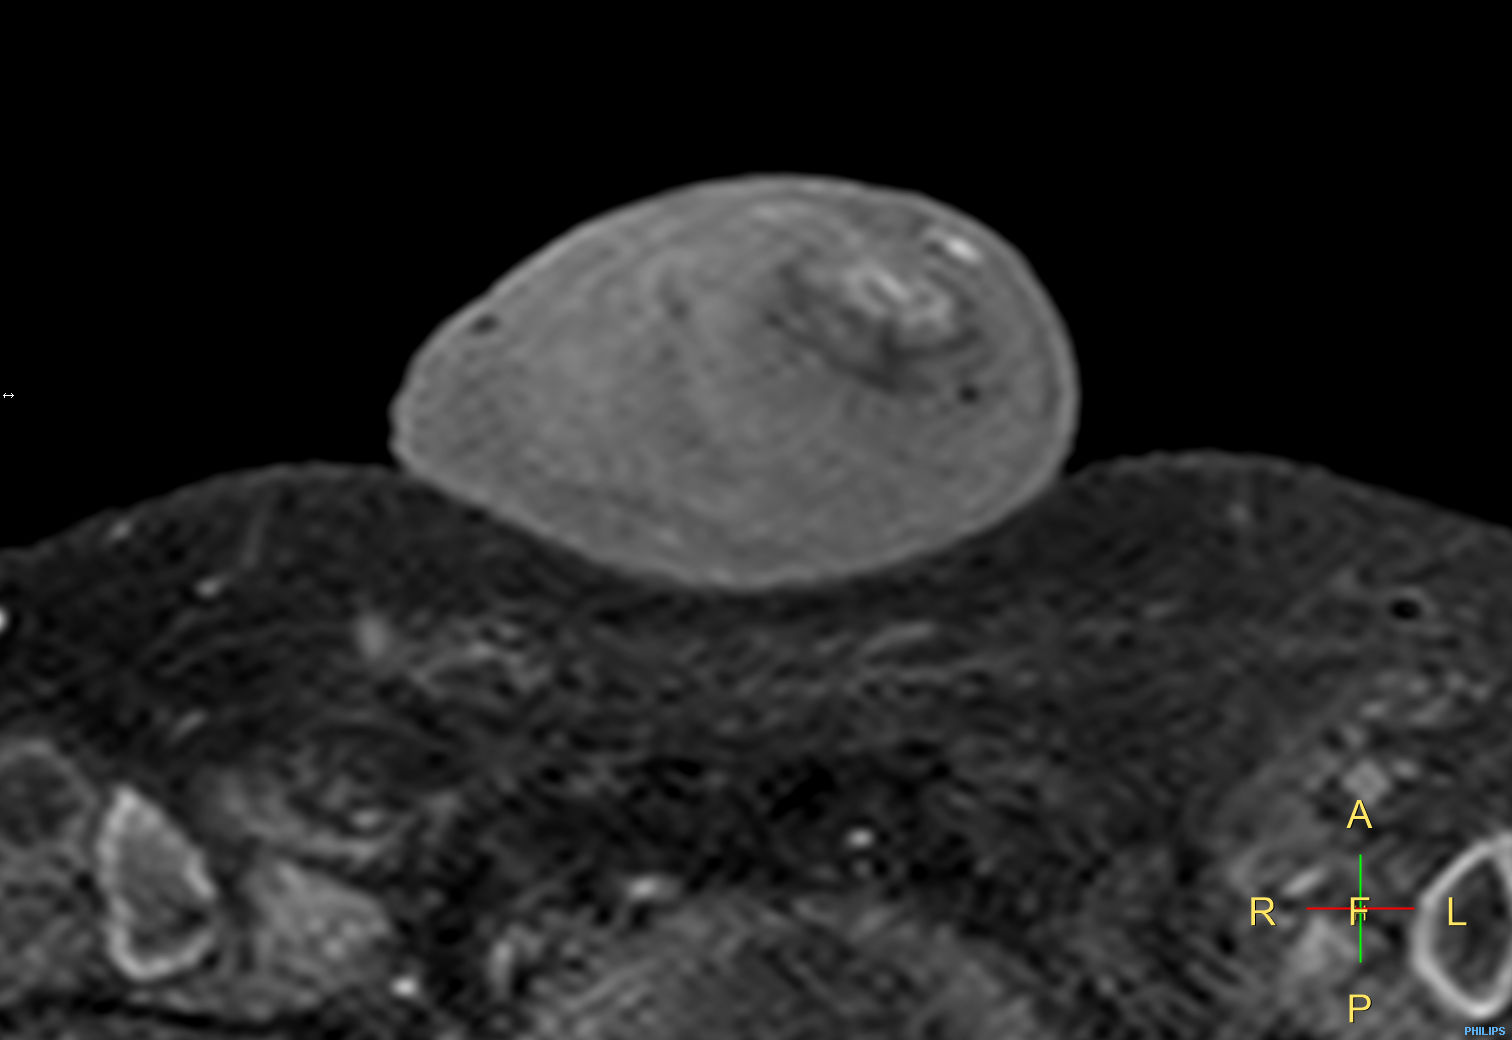

Penile carcinoma

Patient with a penile carcinoma. ExamCard includes Compressed SENSE to shorten exam time, diffusion to achieve high contrast between background and lesions, and MultiVane XD for motion-free imaging in short scan time.

Diffusion (b100)